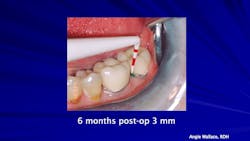

At three months, the patient had reduced pocket depths, but her home care was still a concern.

At six months, the patient’s oral hygiene was improved, and we discussed the importance of investing in an ultrasonic toothbrush.

By the 12-month periodontal maintenance appointment, the patient had her oral hygiene under control. During this time, we continued to maintain her pocket depths with use of the laser. The patient maintained with zero 4 mm pockets and was very happy with the results. See Figures 1–4.